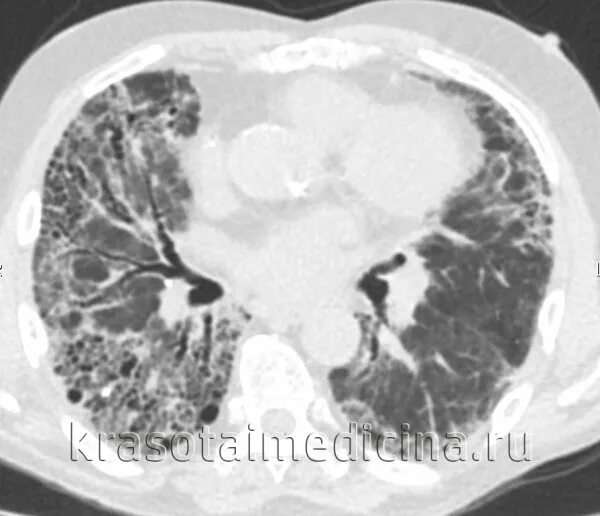

Как лечить пневмосклероз легких в пожилом возрасте